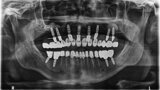

Fig. 31: OPG after exposing implants at the lateral section and having used a temporary prosthesis based on telescopes.